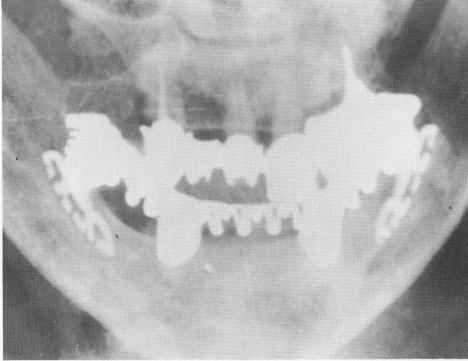

Fig. 11-200. A posteroanterior roentgenogram shows the shoulders of the blade correctly buried 2 mm. below the alveolar crest.

2 Roentgenogram shows shoulders of blade buried below alveolar crest